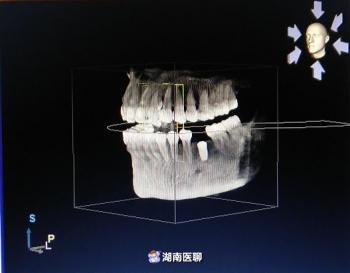

(種植術(shù)前cbct)

(種植術(shù)后cbct)

術(shù)后,經(jīng)口腔CBCT檢查,植入的種植體的三維方向都十分契合。